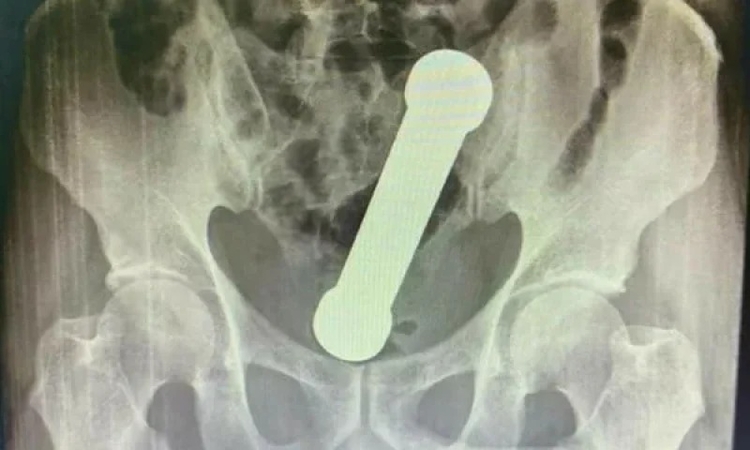

Manaus/AM - Um homem de 54 teve que ser operado em Manaus, após um exame de raio-X detectar a existência de um peso de academia em seu corpo.

Segundo a publicação, o homem procurou uma unidade de saúde da capital amazonense sentido há dois dias fortes dores, náuseas e dificuldade de evacuação. O peso tinha aproximadamente 2 quilos e cerca de 20 centímetros de comprimento.

O haltere estava entre o reto e o intestino grosso do paciente, que, após a surpresa da equipe médica, admitiu ter introduzido o peso de academia no corpo para obter satisfação sexual.

Após tentarem tirar o objeto do paciente com uma pinça cirúrgica, o homem precisou ser sedado e passar por cirurgia. Após três dias de internação, o paciente recebeu alta e se encontra bem.